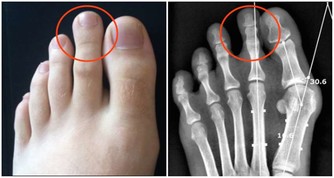

1、關節疼痛、紅腫

大量尿酸結晶沉積關節腔內,可誘發痛風性關節炎。患者往往在深夜突然出現關節疼痛,如刀割般疼痛,嚴重時會影響走路,伴關節紅腫,局部皮膚溫度升高的症狀。

首次發作以第一蹠趾關節(大腳趾與腳掌連接的關節)最常見,佔90%左右,踝關節、膝關節、腕關節、指間關節等也會受累。